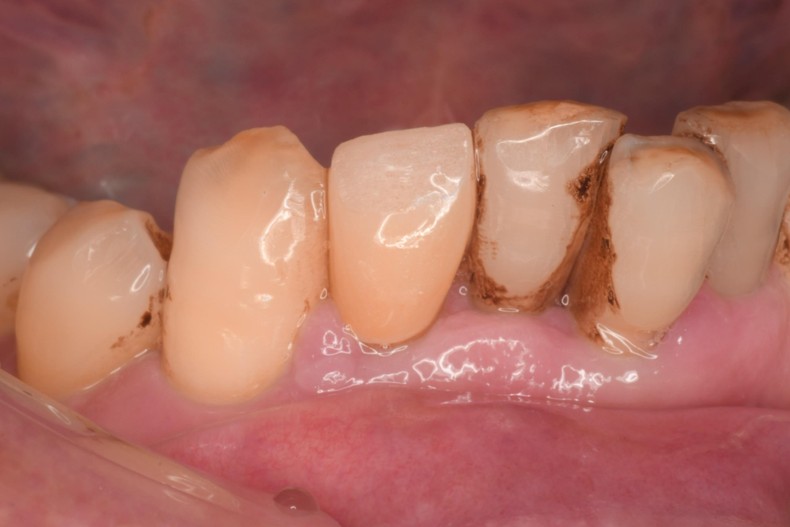

治療前,右下側門牙嚴重牙周病